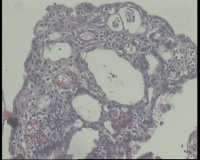

镜下见子宫内膜腺体异型增生,呈乳头状,筛网状排列,细胞核圆形,大小尚均匀,可见少量核分裂像,部分区域鳞化,间质少,部分区域无间质,间质有坏死

有些区域不能除外浆液性癌,最好做一做免疫组化协助鉴别。

浆液性癌!建议P53;P16'ER;PR等确认!